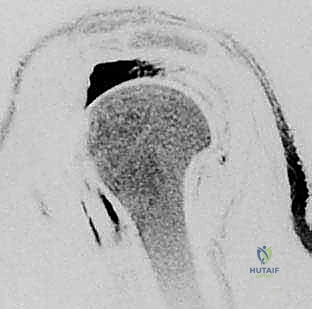

- الرنين المغناطيسي (MRI): هو المعيار الذهبي. يوضح الرنين المغناطيسي حجم التمزق، موقعه، مدى تراجع (انسحاب) الوتر، وما إذا كان هناك ضمور دهني في العضلة.

- الأشعة السينية (X-rays): لاستبعاد وجود كسور، وتقييم المسافة تحت الأخرم، ورؤية النتوءات العظمية أو التكلسات التي قد تكون سبباً في قطع الوتر.